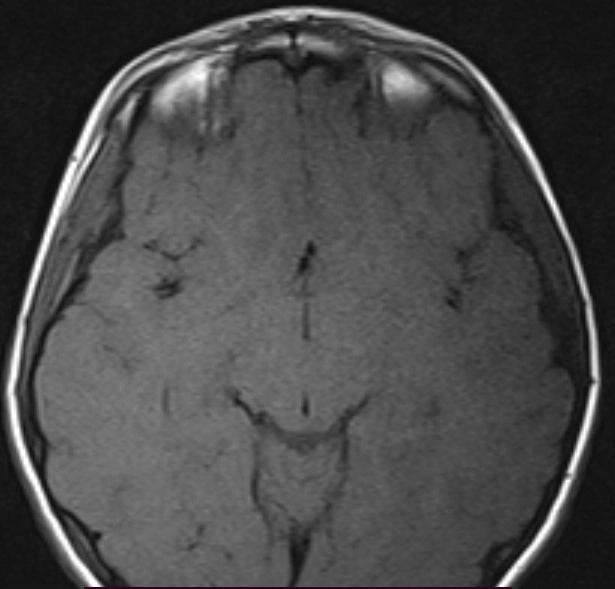

• U lympho hệ thần kinh trung ương (Central Nervous System Lymphoma - CNS Lymphoma)

• U lympho hệ thần kinh trung ương liên quan đến suy giảm miễn dịch (Immunodeficiency-associated CNS lymphomas)